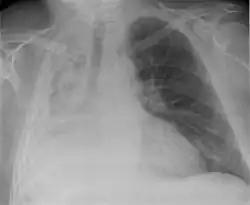

Atelectasis of a person's right lung

Atelectasis is the partial collapse or closure of a lung resulting in reduced or absence in gas exchange. It is usually unilateral, affecting part or all of one lung.[2] It is a condition where the alveoli are deflated down to little or no volume, as distinct from pulmonary consolidation, in which they are filled with liquid. It is often referred to informally as a collapsed lung, although more accurately it usually involves only a partial collapse, and that ambiguous term is also informally used for a fully collapsed lung caused by a pneumothorax.[1]